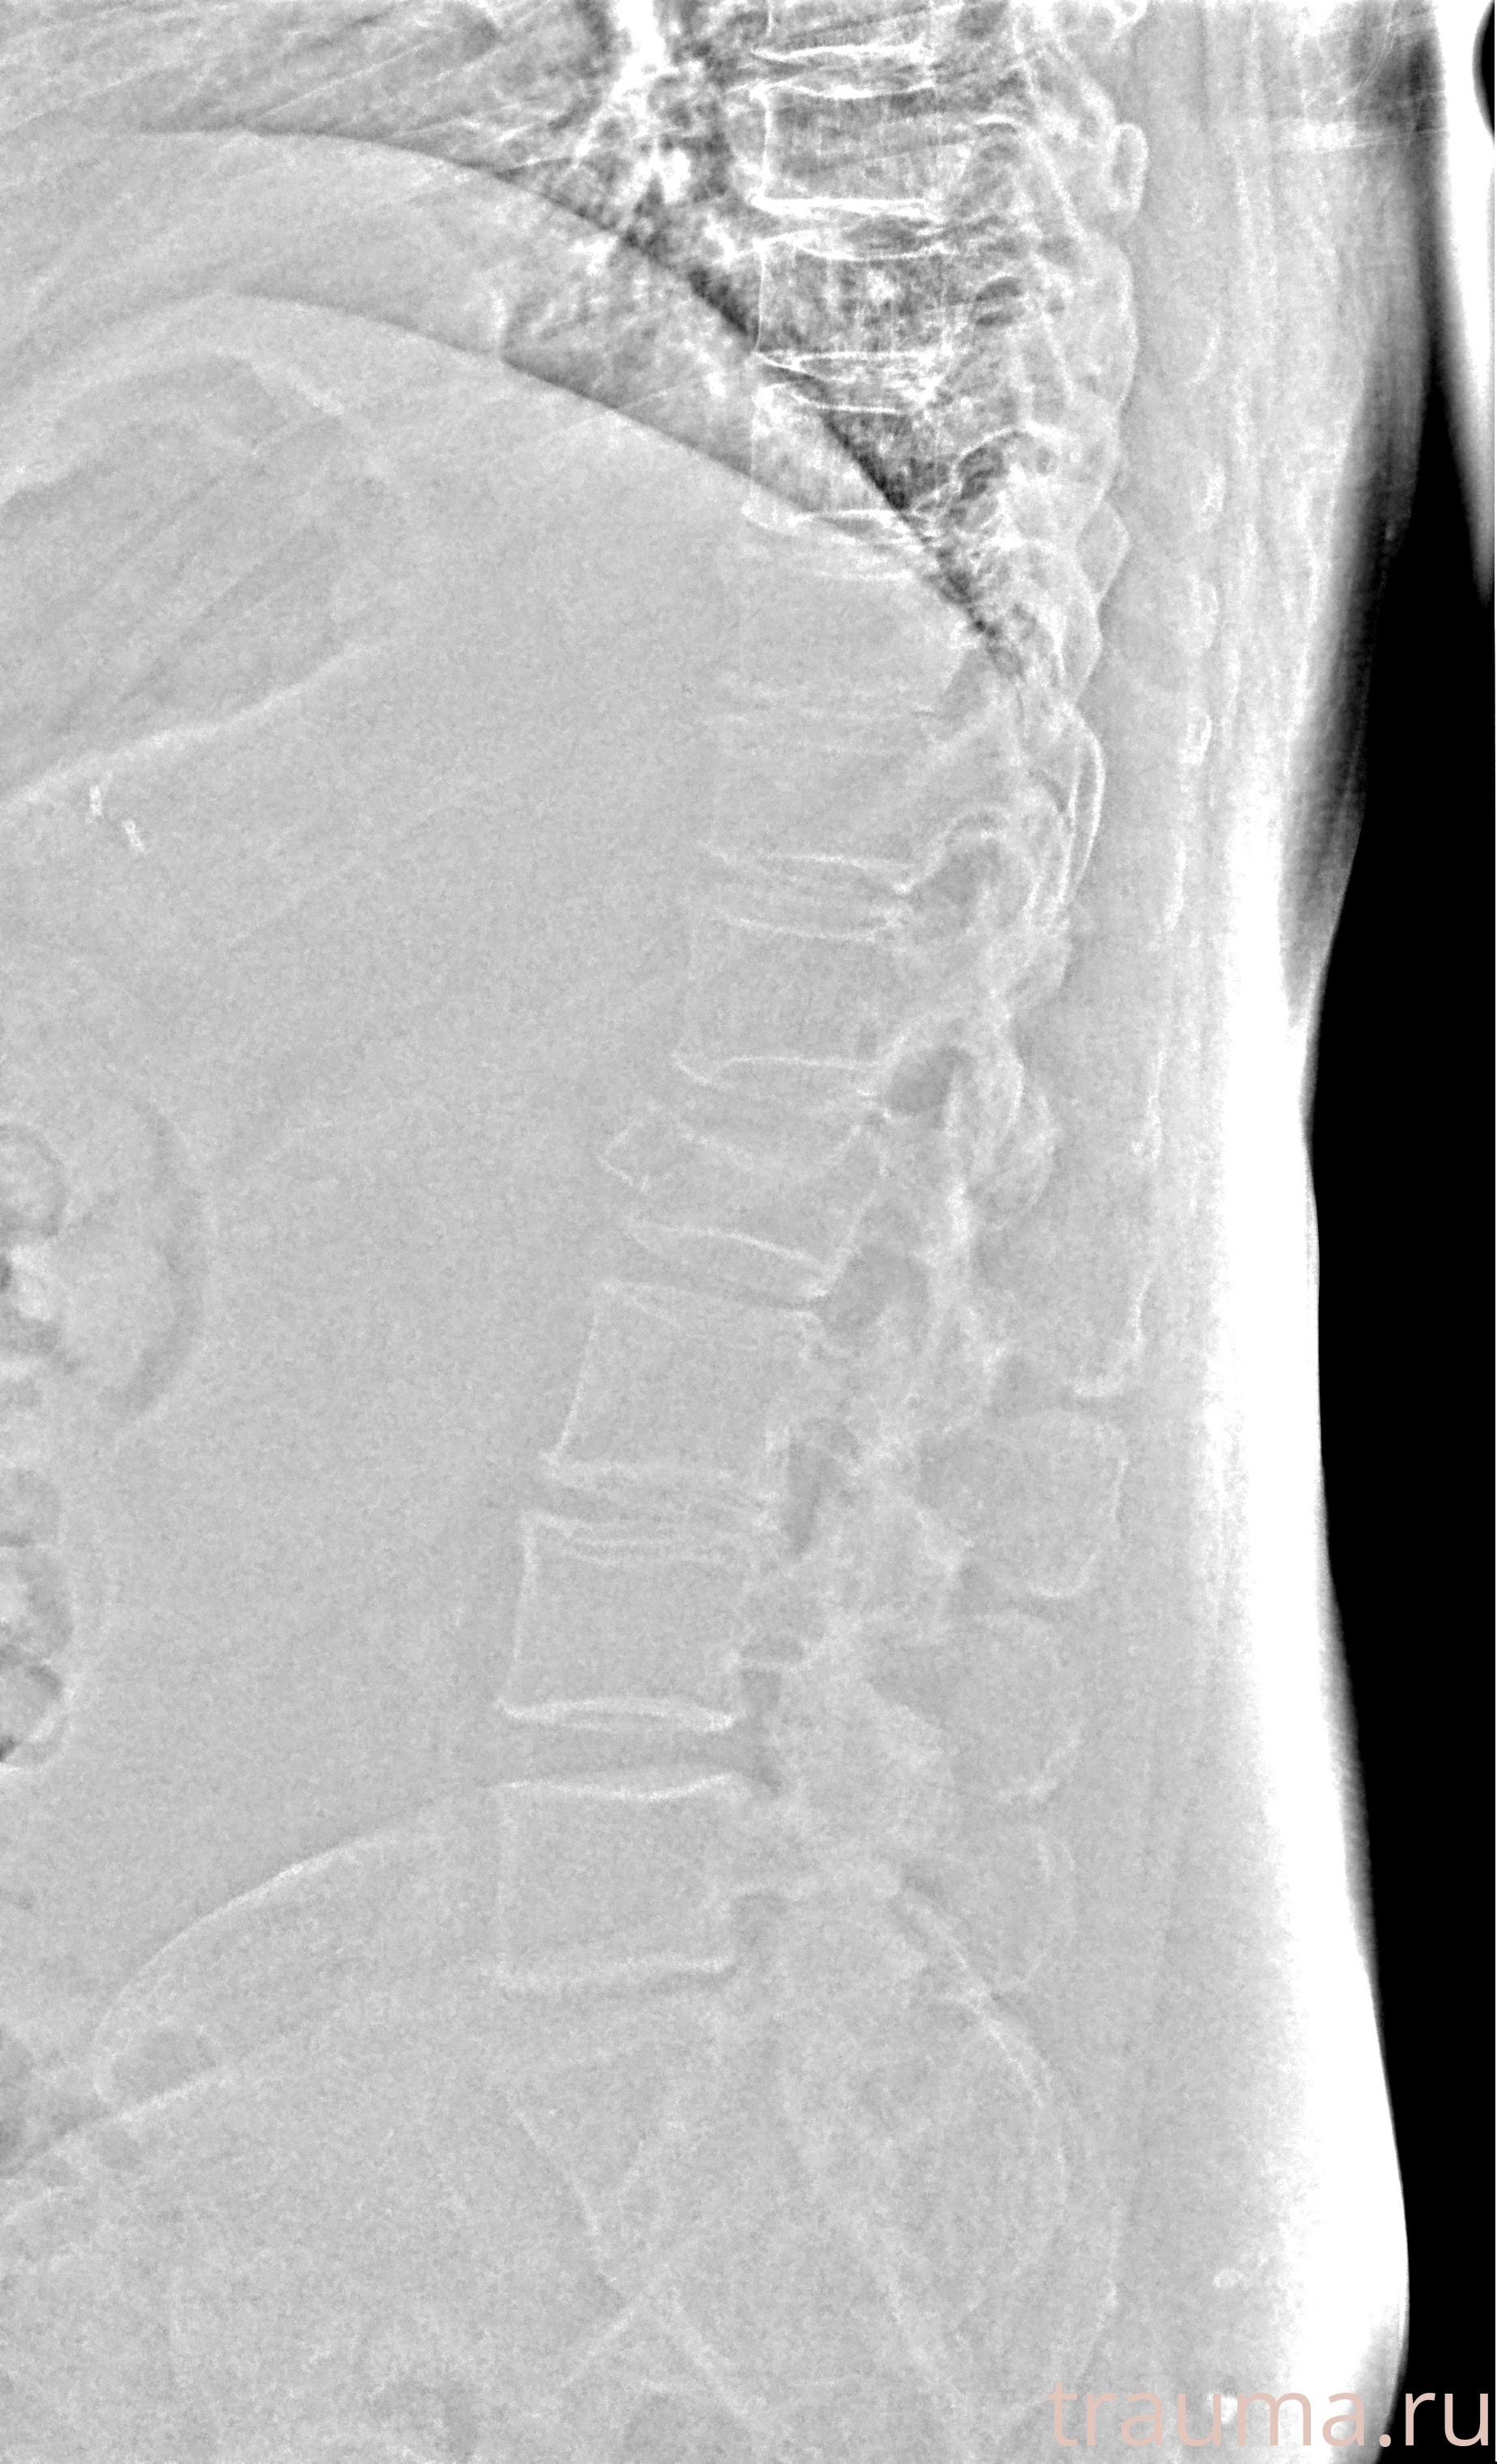

Рентгенограммы

Рентген на дому: по вашему адресу приезжает врач-рентгенолог, травматолог-ортопед с мобильным рентгеновским аппаратом, проводит диагностику травмы или заболевания, делает необходимые рентгенограммы, дает рекомендации по дальнейшему лечению. Получить качественные снимки в домашних условиях возможно благодаря уникальной методике, разработанной МосРентген Центром для института  Склифосовского